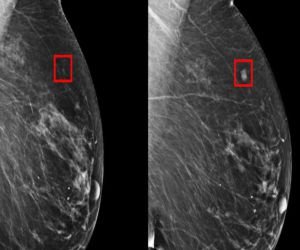

¿Cómo se ve el cáncer de seno en una mamografia?

El tejido mamario denso se ve en la mamografía como una zona blanca sólida, y el tejido adiposo se ve como una zona oscura. Algunos estudios han hallado que las nuevas mamografías digitales detectan mejor el cáncer en las mamas densas que las mamografías que usan una película radiográfica.